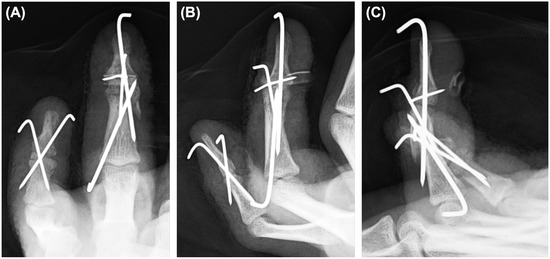

Background and Clinical Significance: Mallet finger is a common injury of the extensor mechanism at the distal interphalangeal (DIP) joint; however, open double mallet lesions are rare and may present a complex reconstruction challenge. Case Presentation: A 15-year-old male high school student who sustained an open injury to the left ring and little fingers after a high-energy buggy accident. The ring finger showed an open double mallet lesion in which the extensor tendon remained attached to a tiny avulsion fragment, and a separate dorsal base fragment was also present. The adjacent little finger had a concomitant open fracture with substantial soft tissue injury. Emergency surgery was performed on the day of the injury. For the ring finger, reduction of the tendon-attached avulsion fragment and separate dorsal base fragment was achieved using extension-block pinning, transarticular DIP pinning, and pull-out fixation over a volar button. For the little finger, cross-pinning was performed because the distal fragment was too small for stable non-transarticular fixation. Serial radiographs showed maintained alignment and progressive healing. At the final follow-up, 21 months after the injury, residual deformity and limitation of DIP motion remained; however, no infection, major skin complications, or nail deformity were observed. The little finger DIP joint became ankylosed, whereas some residual mobility remained in the ring finger DIP joint. Despite persistent functional limitations, the patient was able to continue school attendance and percussion-related activities. Conclusions: This case highlights that in an open double mallet lesion, disruption of both the tendon-attached fragment and its bony bed should be considered, and stabilization of the base may be useful in selected injury patterns before definitive tendon-side repair. Full article